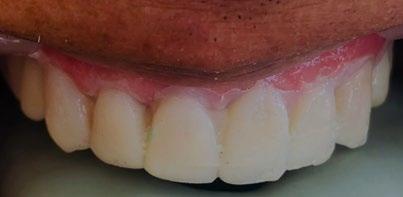

En los estudios finales en las fotografías intraorales (Figura 9) se ve la línea media coincidente, el overjet y el overbite. La alineación y forma de las arcadas superior e inferior, con el

Figura 9. Lateral derecha frente, izquierda final.

Figura 10. Oclusal superior inferior final.

retenedor fijo de premolar a premolar (Figura 10).